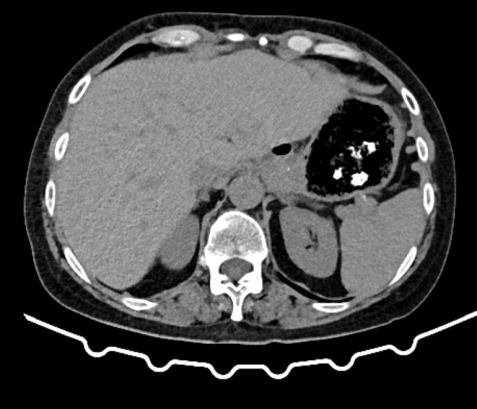

Different views of a double contrast-enhanced CT scan showing a left diaphragmatic hernia with an acute dilated stomach (Courtesy Dr. V. Penopoulos)